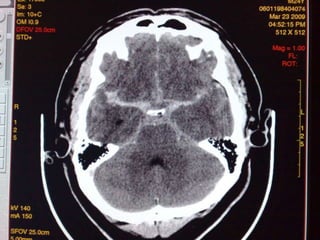

Hemorragia Sub-aracnoidea

 Lesion de vasos perforantes de la pia y

aracnoides

   Mas frecuente en los extremos de edad

   Hiperdensa en la tomografia computada

   Ocupacion de cisuras, surcos y cisternas

   Complicaciones:

hidrocefalia comunicante

vaso-espasmo, isquemia

Hemorragia Sub-aracnoidea  Lesionde vasos perforantes de la pia y aracnoides  Mas frecuente en los extremos de edad  Hiperdensa en la tomografia computada  Ocupacion de cisuras, surcos y cisternas  Complicaciones: hidrocefalia comunicante vaso-espasmo, isquemia

Hueso dura aracnoides Pia cerebro Hemorragia sub-aracnoidea sutil difusa inter-hemisferica intra-ventricular